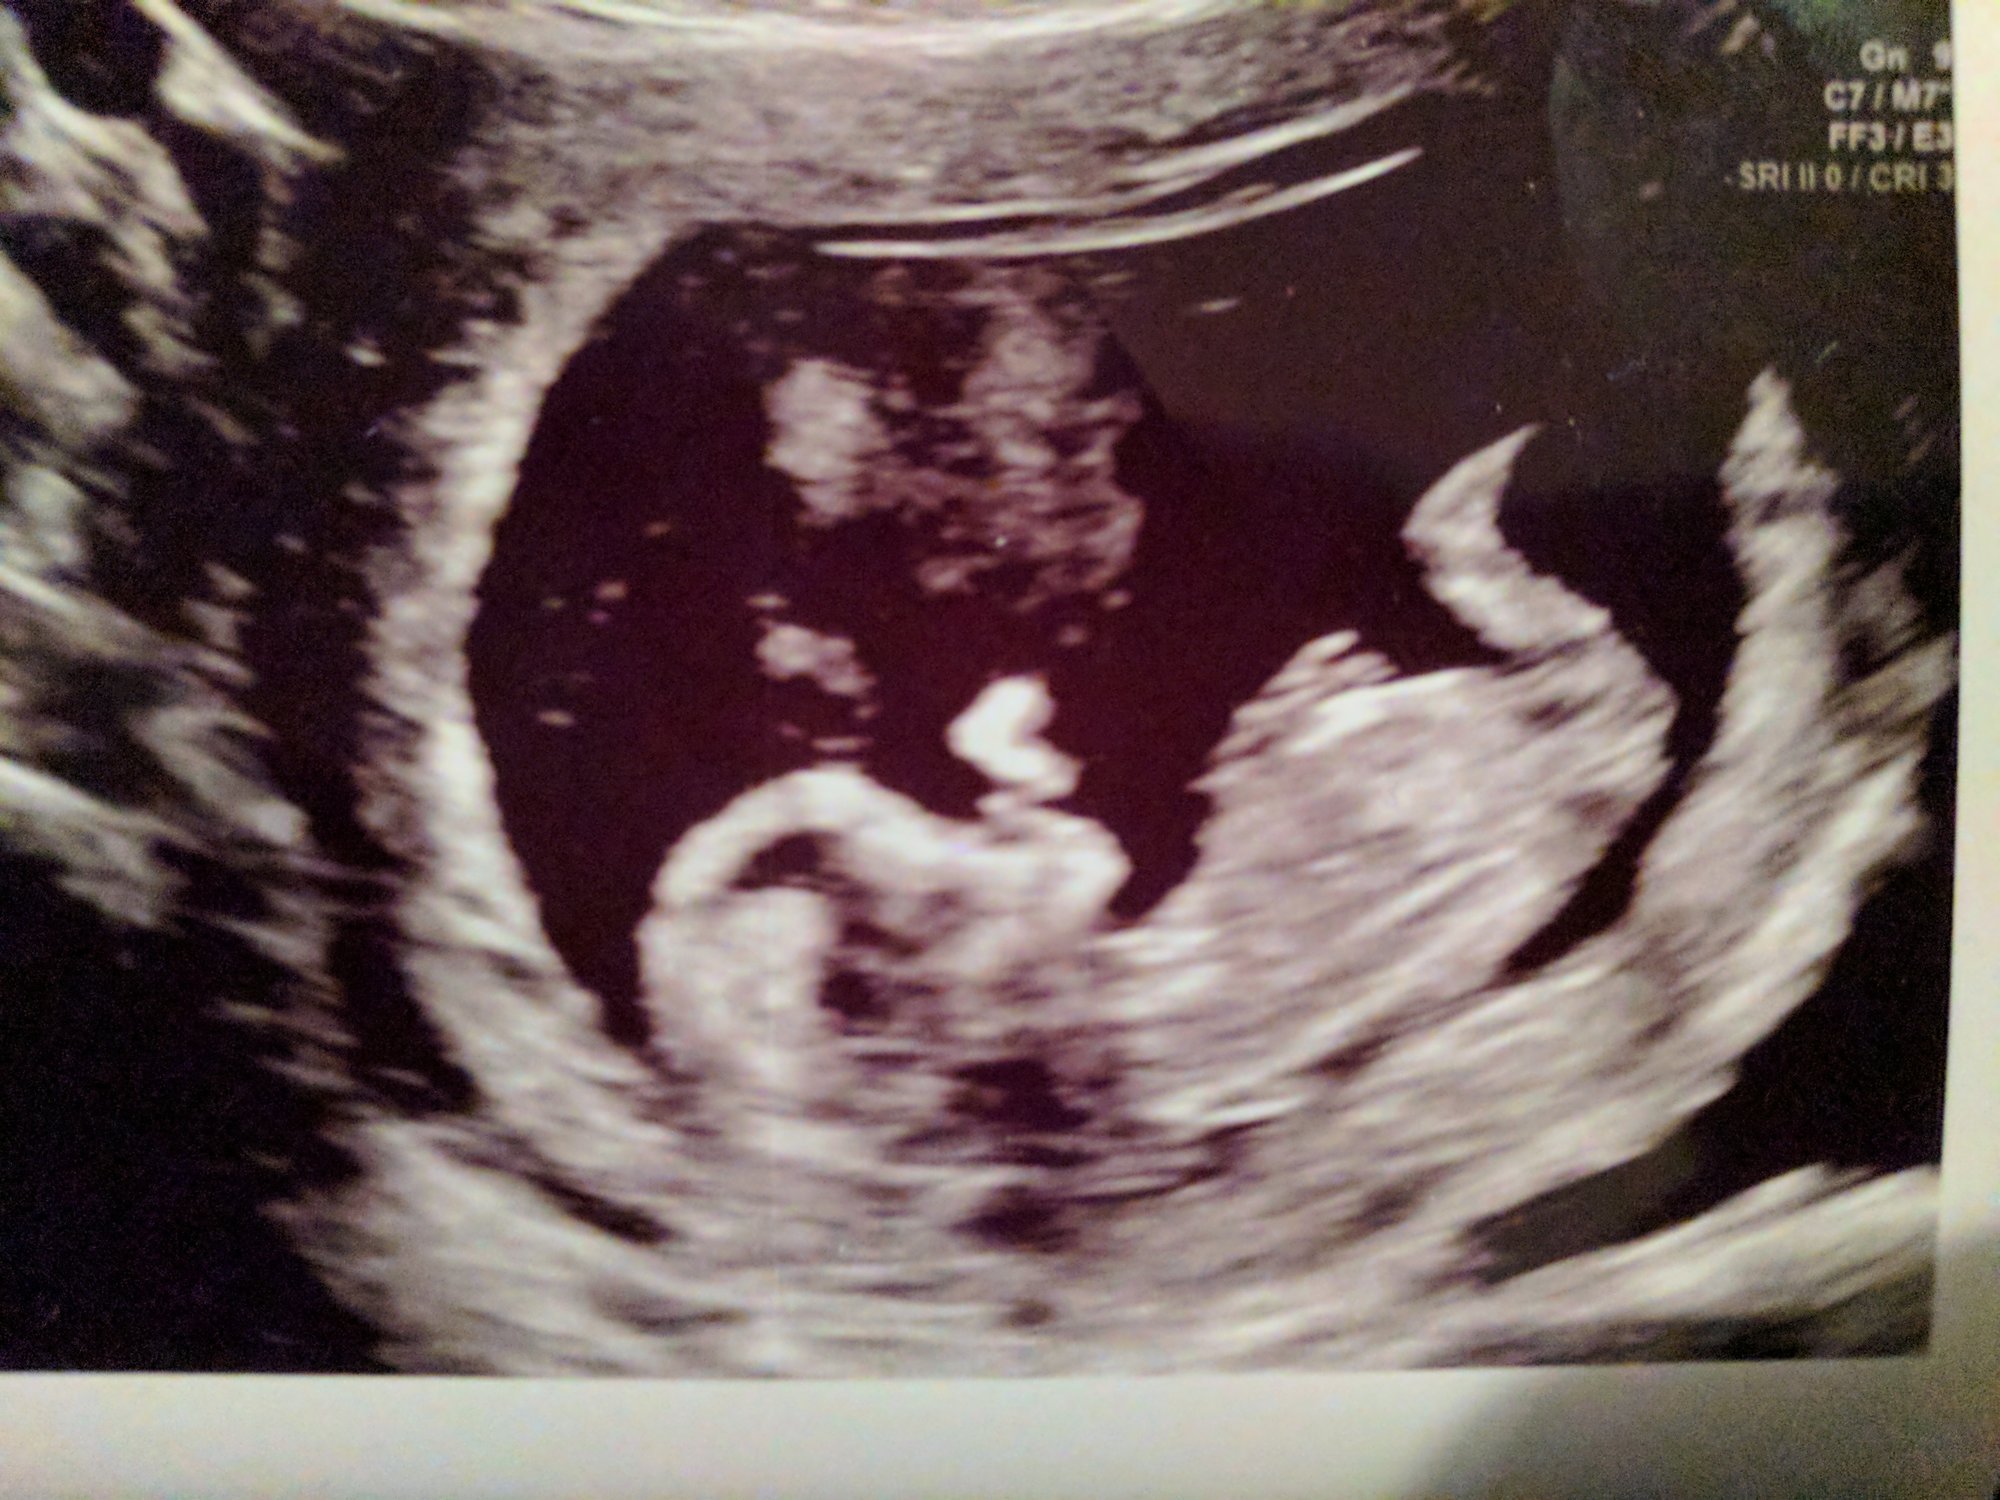

9w5d measuring at 10w1d. HR 167. Our little gummy bear was wiggling all around and even kicked for us quite a bit. They also kept bringing their hand to their mouth...it's so crazy to see what's happening inside! It's starting to look like a real human.